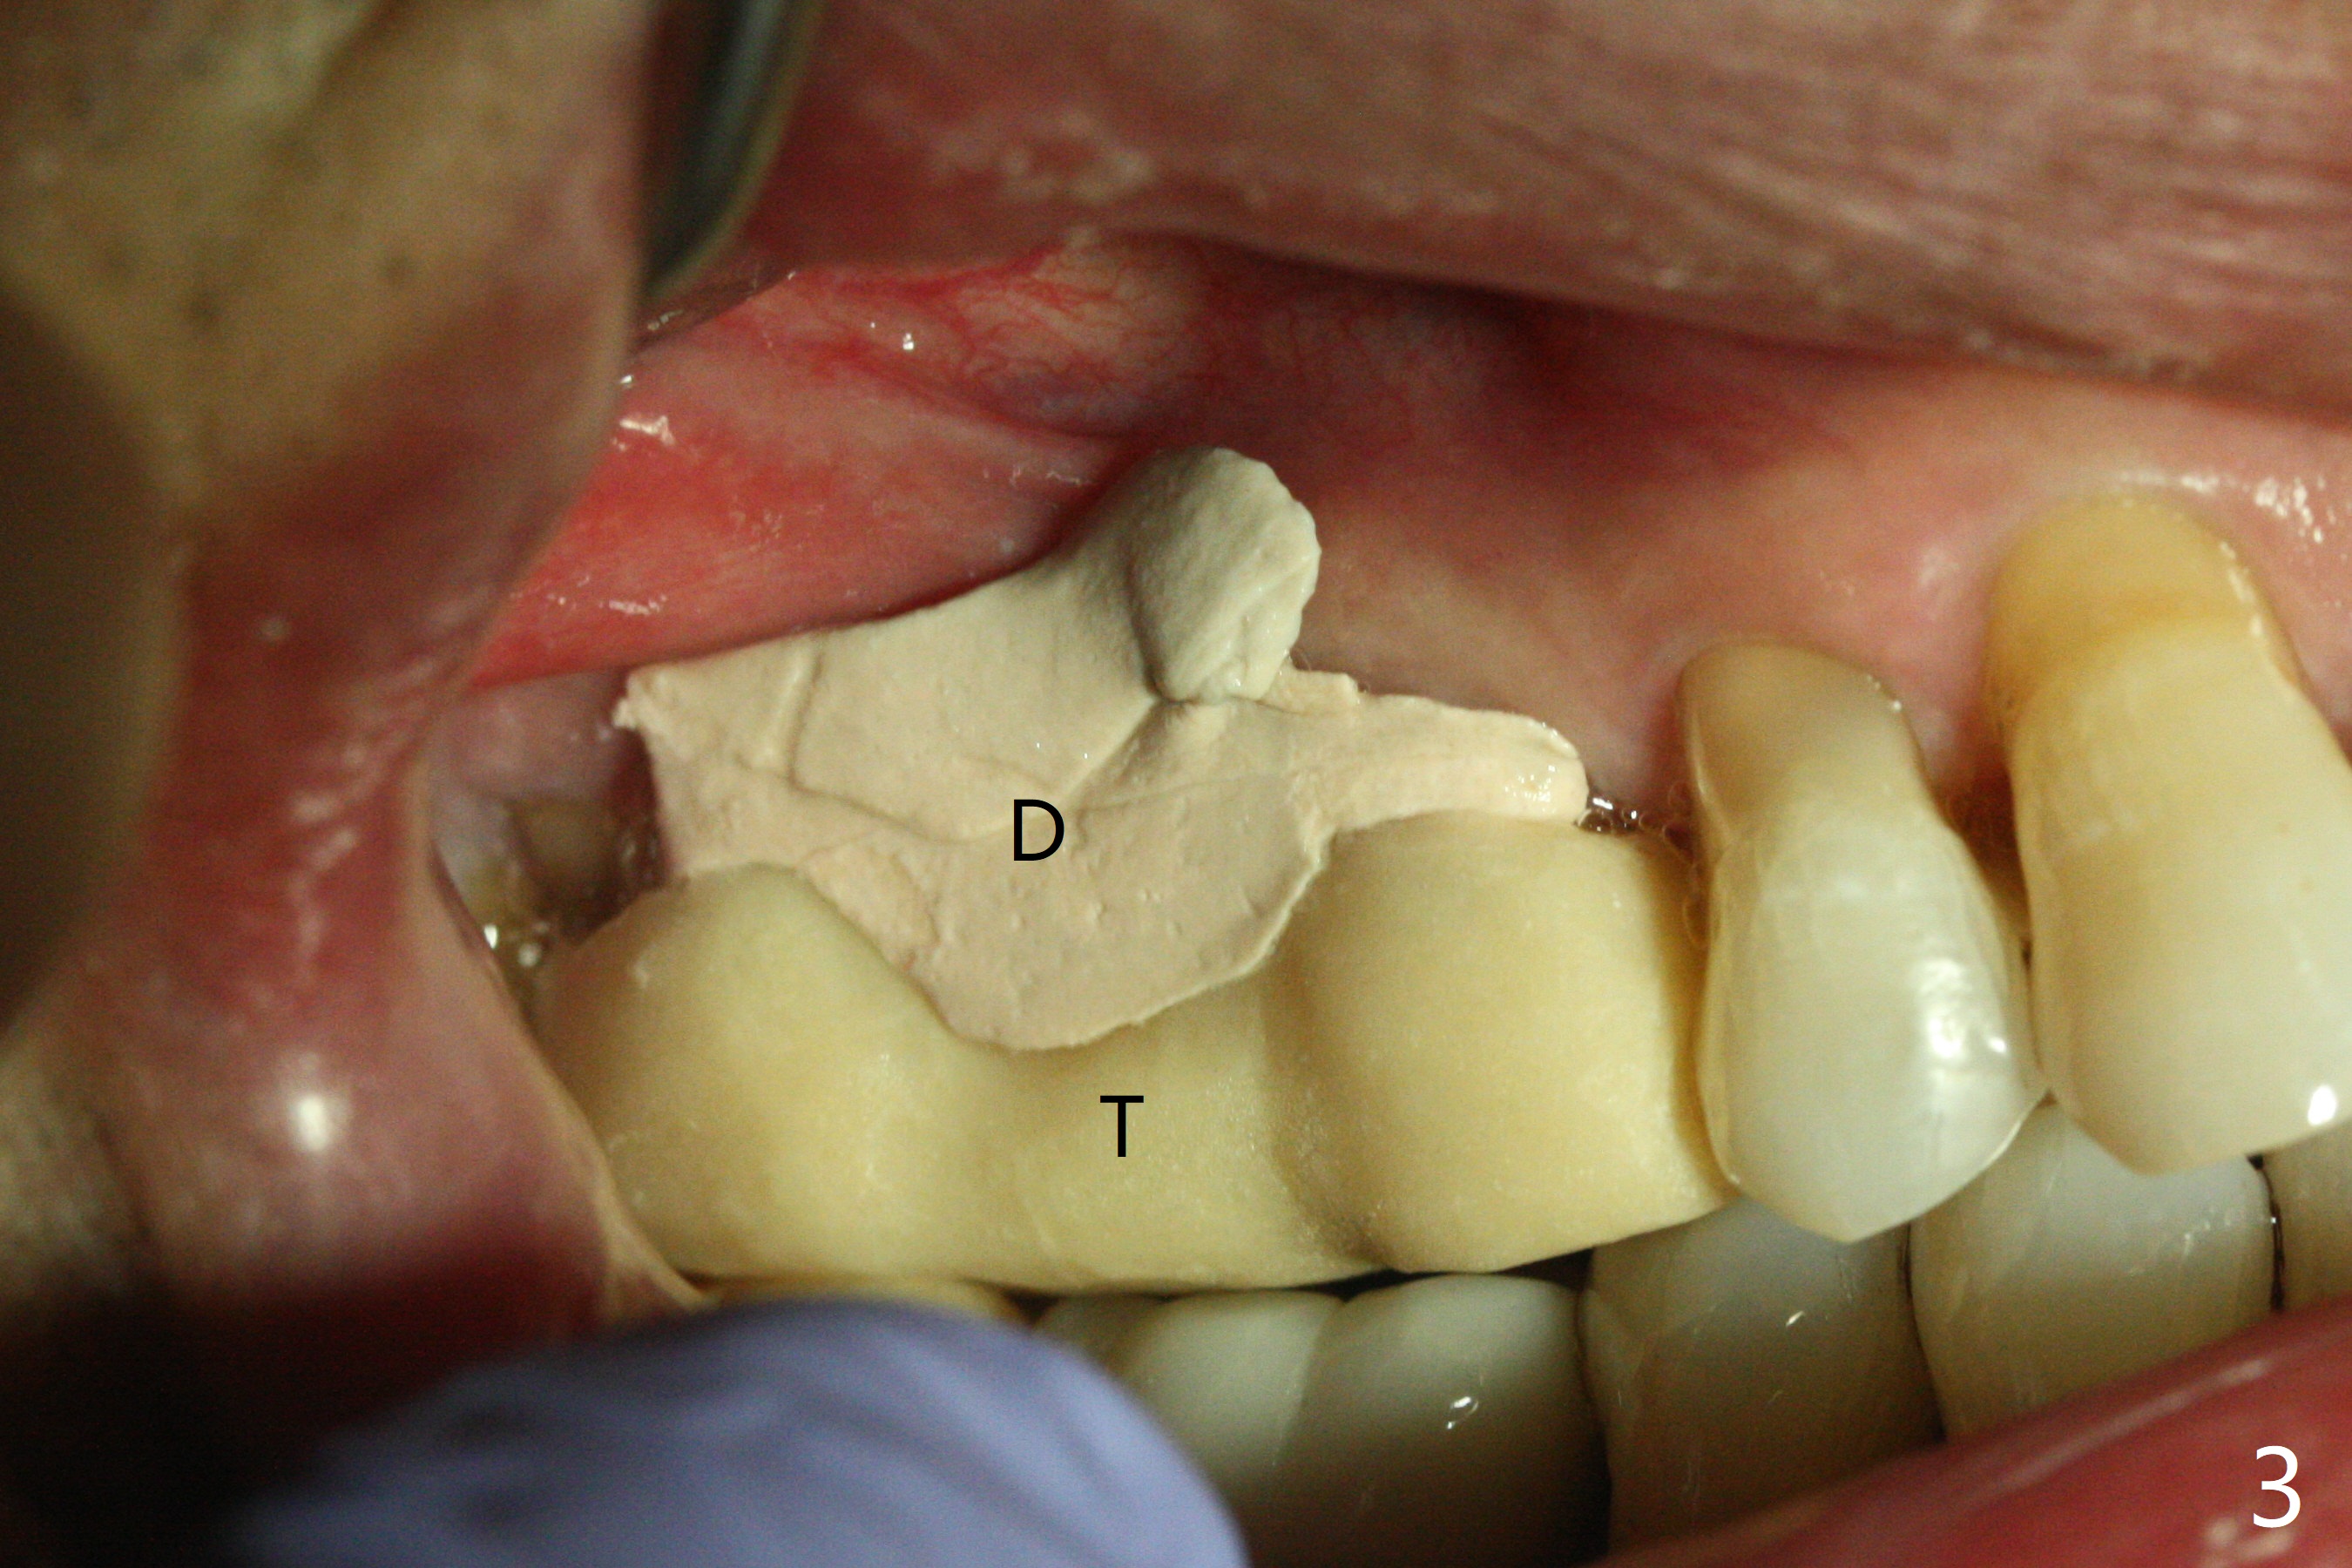

After osteotomy at #3 with IS guide, a 4.5x8 mm SM implant has to be placed free hand because of mismatch of the SM implant and IS guided fixture driver. With minor adjustment, the implant is placed subcrestal to reduce chance of future periimplantitis (Fig.1,2). There is oozing in the osteotomy, which seems to stop when the implant and healing abutment are placed. The patient returns with oozing next day. The temporary FPD is removed. The oozing is coming from the area around the healing abutment. Gauze pressure appears to be effective. After application of periodontal dressing (Fig.3 D) around the healing abutment, the temporary FPD is inserted (T). Hemostasis occurs. Fig.3 is taken 7 days postop. The implant remains subcrestal 3 month postop (Fig.4). A 5.8x7(3) mm cemented abutment is placed for a separate provisional.